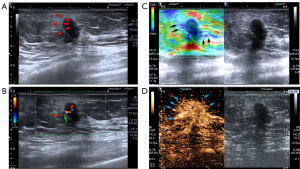

Conventional US assessment was conducted following the guidelines of the American College of Radiology’s Breast Imaging Reporting and Data System (BI-RADS). Since this study focused on the PA, the evaluation of suspected lesions mainly included tumor size (maximum diameter), margin definition (circumscribed or not circumscribed), presence of echogenic halo (present or absent) (Figure 1A), and peritumoral vascularity (present or absent) (Figure 1B).

For UE assessments, we used the Breast Strain UE Evaluation Methods and Optimal Thresholds outlined in the 2018 European Federation of Societies for US in Medicine and Biology (EFSUMB) Guidelines and Recommendations on the Clinical Use of US UE (17). The process entailed computing the ratio derived from the lesion size observed in UE divided by the lesion size as identified in B-mode US (E/B ratio). The evaluation was aimed at identifying suspected lesion areas with an enlarged, stiff area (Figure 1C). A ratio greater than 1 was considered to indicate the presence of an enlarged stiff area, while a ratio of 1 or less indicated an absence. Additionally, the assessment extended to measuring the elastic strain ratio between the 1 cm periphery around the tumor’s edge and the distant normal tissue (comprising glandular tissue and surrounding fat tissue), with 3 serving as the critical threshold. Measurements were obtained three times to derive an average value for accuracy.

CEUS evaluation included an analysis of both qualitative and quantitative parameters. Qualitative parameters included the peritumoral zone boundary (clear or blurred), penetrating vessels (present or absent), enhancement intensity (hypoenhancement or not), enhancement scope [enlarged or not; enlargement scope was defined as an increase of ≥3 mm in length or width as compared to conventional US measurements (18-20)], and radial peripheral perfusion (present or absent; radial peripheral perfusion was defined as a spoke-wheel pattern extending outward from the lesion (21,22) (Figure 1D).

In the conventional US presentation of the PA in breast cancer, a significant difference was observed in the incidence of echogenic halos (Figure 1A), with 78.8% (41/52) in the RS >25 group and 55.6% (79/142) in the RS ≤25 group (P=0.003). No significant differences were found between the groups in terms of margin (P=0.326) or peritumoral vascularity (P=0.531) in the PA (Table 2).

In UE, the proportion of an enlarged stiff area in the PA was 76.9% (40/52) in the RS >25 group, which was significantly higher than the 56.3% (80/142) in the RS ≤25 group (P=0.009) (Figure 1C). However, the elastic strain ratio in the PA showed no significant difference between the groups (P=0.588).

In CEUS, the incidence of patients showing enlarged enhancement scope was significantly higher in the RS >25 group (43/52, 82.7%) than in the RS ≤25 group (P=0.010) (Figure 1D), as was radial peripheral perfusion (65.4%, 34/52) (P=0.047). No significant differences between the two groups were noted in terms of boundary (P=0.139), penetrating vessels (P=0.562), or enhancement intensity (P=0.276). In terms of quantitative parameters, the RS >25 group exhibited higher PI values (P=0.038) and lower TTP values (P=0.030) compared to the RS ≤25 group, while other characteristics including MTT (P=0.244), sharpness (P=0.111), AUC (P=0.719), AWI (P=0.365), and AWO (P=0.883) showed no significant differences between the two groups.